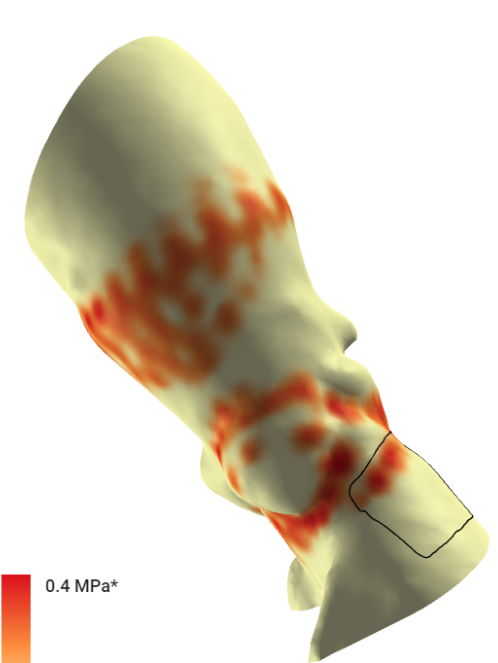

L26号瓣膜高位植入后主动脉受压情况

L26号瓣膜标准位植入后主动脉受压情况

根据FEops评估报告得知,L26号瓣膜在高位和标准位释放之后,分别会发生21%和29%的接触压力指数,均大于FEops评估有无传导阻滞的临界值14%,其中L26号瓣膜高位释放结果虽然比标准位释放结果略好,但是发生传导阻滞的可能依然很大,建议术中使用A+减少风险,必要时术后留置起搏器观察。